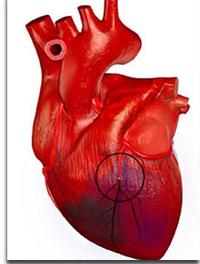

Chaque année, des dispositifs électroniques cardiaques implantables (DECI) sont implantés chez environ 1,5 millions de patients à l’échelon [...]

Après des débuts encourageants il y a déjà 10 ans, la thérapie cellulaire cardiaque n’a pas tenu toutes ses promesses. Les études cliniques [...]

AHA – Chicago. L’essai MAGIC (Myoblast Autologous Grafting in Cardiomyopathy) est la première étude randomisée destinée à évaluer les [...]

La thérapie cellulaire des infarctus du myocarde (IDM) est une véritable quête du Graal dans laquelle se sont lancées depuis 2001 quelques [...]